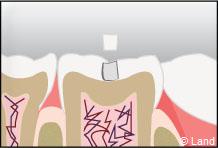

Un inlay reconstitue l’anatomie dentaire en comblant une cavité taillée dans la dent.

Inconvénient mineur : sauf dans certains cabinets équipés en CFAO (Conception et Fabrication Assistées par Ordinateur), cette technique nécessite 2 séances de soins, car une étape de laboratoire s’intercale entre la réalisation de la cavité et la pose et le scellement des inlays onlays réalisés en métal, en résine composite ou en céramique.